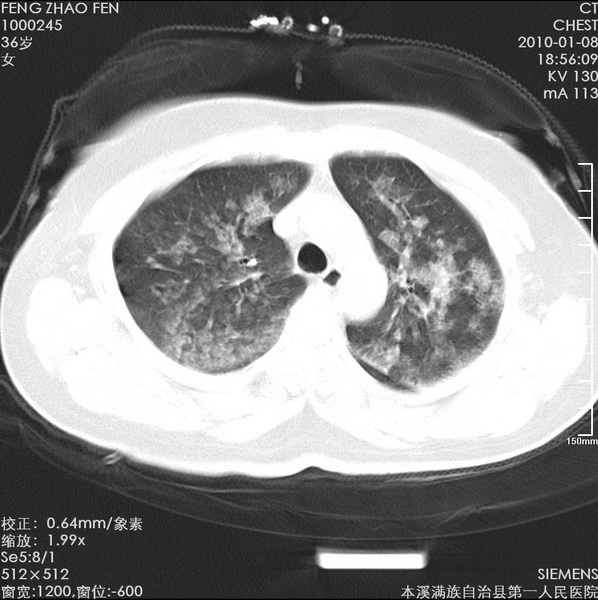

标题: CT24051:双肺多发斑片状阴影 [打印本页]

标题: CT24051:双肺多发斑片状阴影

女、36、咳嗽、咯血,余不详。